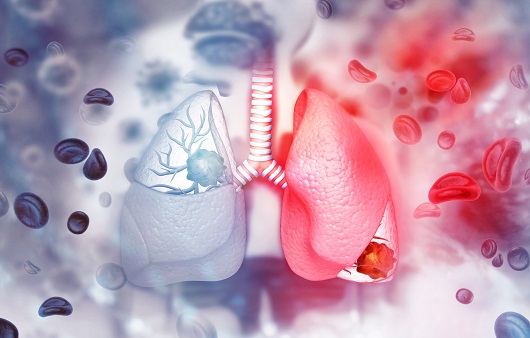

둘째, 환경적 요인이 '폐암'으로 이어질 수 있습니다. 일상 생활에서 흡입되는 발암 물질은 폐암을 유발할 수 있습니다. 즉, 대기오염 가스 중의 발암물질을 흡입하거나 흡연을 통한 발암물질을 직간접적으로 흡입함으로써 폐암이 발생할 수 있습니다. 흡연은 폐에 매우 치명적이어서 흡연은 폐암의 가장 큰 원인이며, 비흡연자도 간접흡연으로 폐암에 걸릴 수 있습니다.

흡연자가 주변에 있으면 비흡연자도 영향을 받는다는 연구 결과가 있습니다. 폐암은 다른 많은 환경적 요인으로 인해 다양한 원인이 있습니다. 또한 폐암은 주로 노인에게 영향을 미치며 40세 미만보다 70세 이상 인구가 더 많습니다. 따라서 나이가 들어감에 따라 정기적인 건강 검진이 필수적입니다.

이러한 폐암의 원인으로 인해 폐암으로 진단되기 전에 폐암 초기증상을 조기에 발견하면 다른 장기로의 전이나 진행성 폐암으로의 진행을 어느 정도 지연시키거나 적절하게 치료할 수 있지만 일반적으로 폐암의 초기 단계는 특별한 징후나 증상이 없으므로 조기에 발견하는 경우는 극히 드뭅니다.